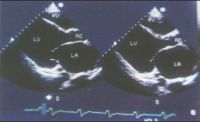

3.超声心动图:在本病早期即可见到心腔轻度扩大,尤其左心室,室壁运动减弱,后期各心腔均扩大,室间隔与左室后壁运动也减弱。二尖瓣前叶双峰可消失而前后叶呈异向活动。左室喷血比数常减至50%以下,心肌缩短比数也减小。可能有少量心包积液。

扩张型心肌病超声心动图表现

扩张型心肌病患者由于心肌病变、心脏扩大、左心室扩张或双心室扩张,引起左心室收缩功能障碍,出现收缩性心力衰竭。随着病程进展,发生右心衰或全心衰。扩张型心肌病并发心力衰竭的超声心动图特点: ①左室扩大。由于广泛心肌病变,四个心腔均有不同程度的扩大,以左室呈球型样扩大为著,室间隔向前膨出,较主动脉前壁位置前移,而乳头位置向后侧移位,与主动脉后壁不在同一水平上,M 型示主动脉前壁向室间隔延续,室间隔向前膨出而主动脉后壁与二尖瓣前叶相延续时,二尖瓣前叶位置向后移位,二者形成“喇叭口”状,左室流出道增宽。②二尖瓣改变。由于心肌收缩力减弱,左室舒张压较高,二尖瓣流量减少,二尖瓣运动幅度减低,与增大的左室腔呈“大心腔小开口”改变。③心室壁运动减弱。左室壁普遍变薄呈一致性活动幅度弥漫性减低。